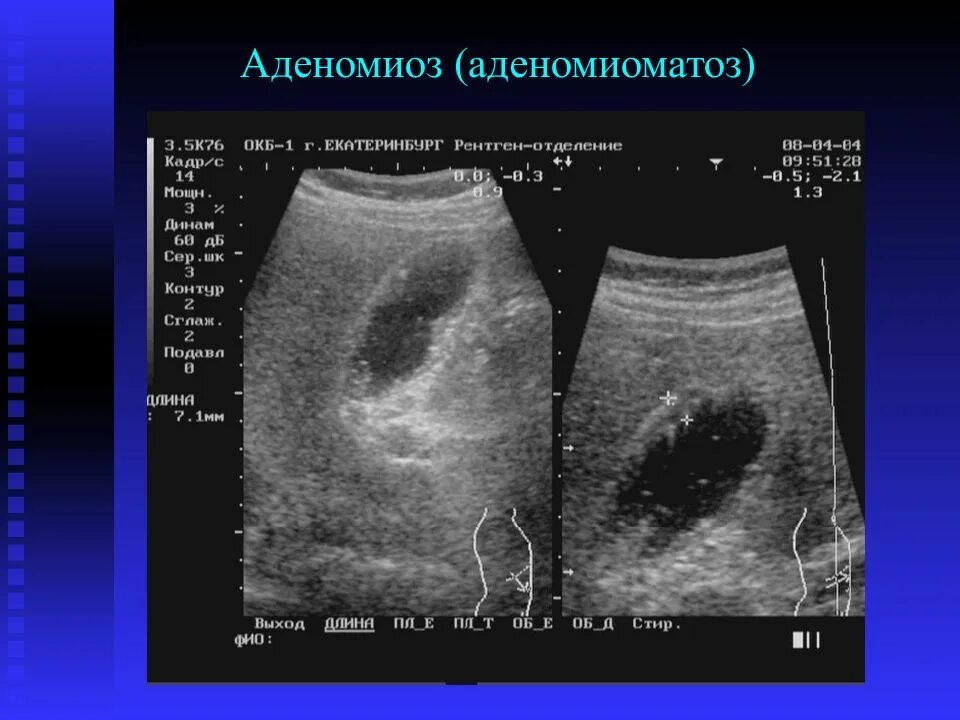

Изменение стенок желчного пузыря